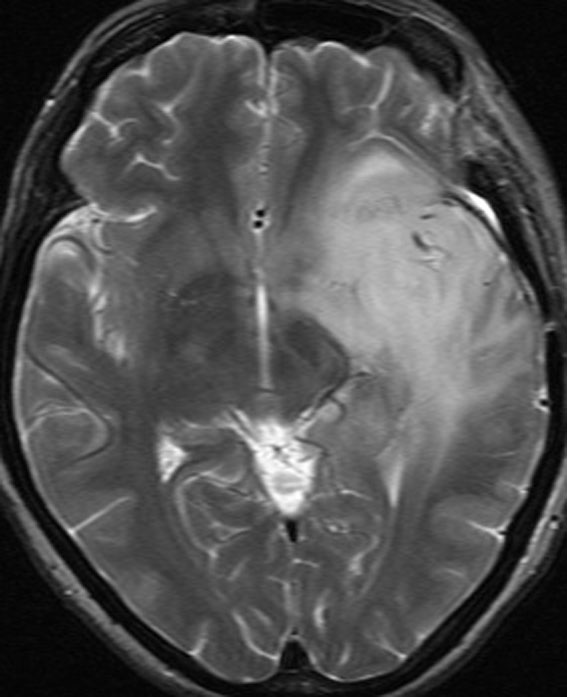

diffuse, infiltrative びまん性のもの

染み込むように左前頭側頭葉から島回に広がるAAです。T2/フレア像でにじむように広がり,ガドリニウム増強されません。グレード 2 (びまん性星細胞腫)と区別が難しいものです。

もちろん手術摘出できないもので,生検手術のみを行います。この大きさのものに60グレイの放射線治療をすれば高度の認知機能低下は避けられませんから,患者さんと照射線量をよくよく相談します。でもAAは放射線化学療法で長期生存が望めます。50-54グレイの線量が選択されます。